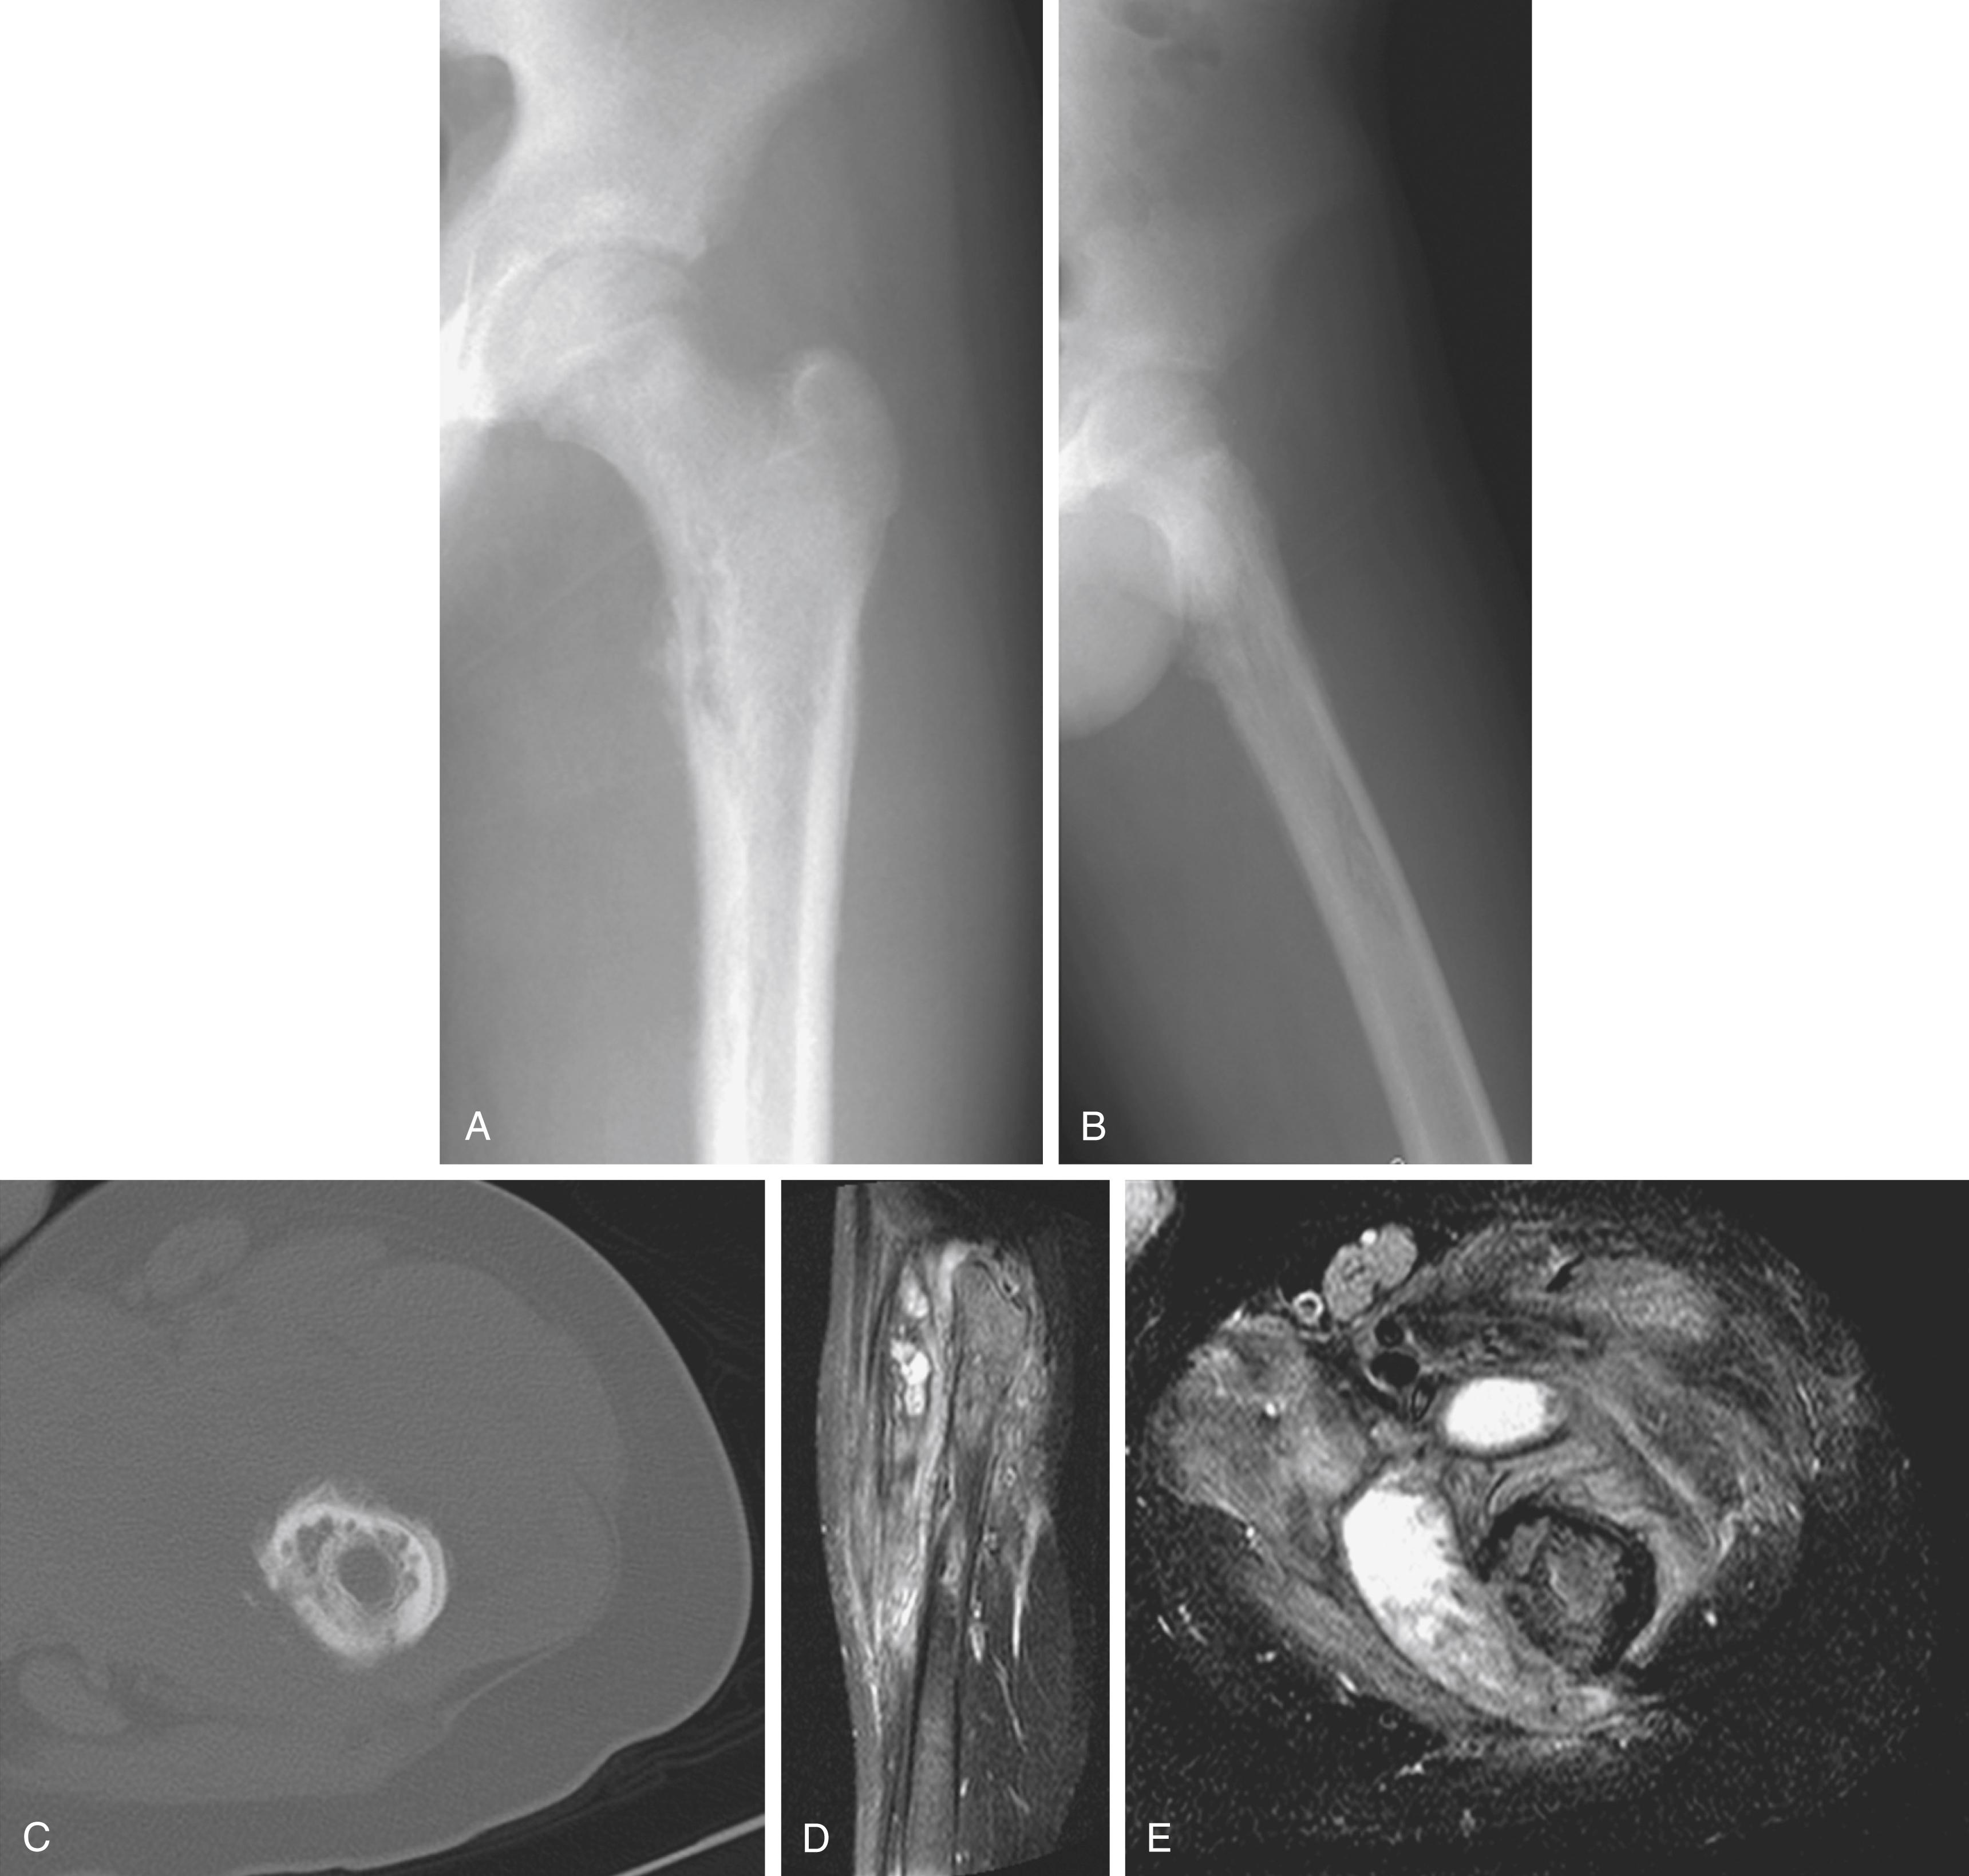

The clinical and radiographic similarities between osteomyelitis and Ewing sarcoma are well known ( Figs. 23.2 and 23.3 ), , , and the pitfall of mistakenly treating Ewing sarcoma with open irrigation and débridement should be kept in mind. One reasonable recommendation is to obtain a bone biopsy by trocar at the same time bone is aspirated for cultures. This simple procedure, which can be performed with an 11-gauge bone marrow biopsy needle, helped identify 1 case of Ewing sarcoma among 30 children with a presumed diagnosis of osteomyelitis in a reported series.

FIG. 23.2, (A) Anteroposterior radiograph showing a lytic lesion in the proximal femur. The patient had a 2-month history of pain and an elevated erythrocyte sedimentation rate. The permeative nature of the lesion suggested a neoplastic rather than an infectious cause. (B) Axial magnetic resonance image of the proximal femur demonstrating a large soft tissue mass posteriorly. Biopsy confirmed the diagnosis of Ewing sarcoma.

FIG. 23.3, Fifteen-year-old boy with a 20-pound weight loss and nighttime pain in the left hip of 3 months’ duration. (A and B) Plain radiographs show poorly permeative lytic changes in the left proximal femur. (C) Computed tomography scan of the area of involvement demonstrates permeative cortical erosions with periosteal reaction. (D and E) Magnetic resonance images show diffuse femoral marrow signal changes with a fluid collection adjacent to bone suggestive of abscess rather than liquefied tumor necrosis. Biopsy and culture confirmed the diagnosis of subacute osteomyelitis with methicillin-resistant Staphylococcus aureus.